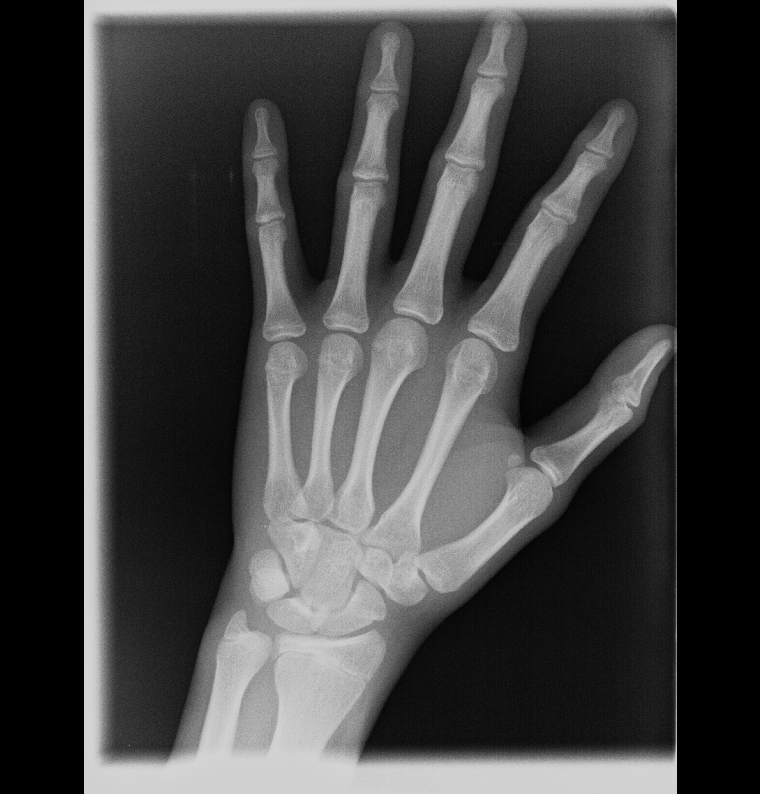

The x ray shows my hand is closing but I heard that knee growth plates close later

Hand doesn't even look close to closing you're probably fine for now, but I would still start using pharmaceuticals

U fr? If I look at indicators on google it looks pretty close to me

Yours still has a very obvious gap indicating some growth left, which is why I said I would start using pharmaceuticals if I were you to maximise that.